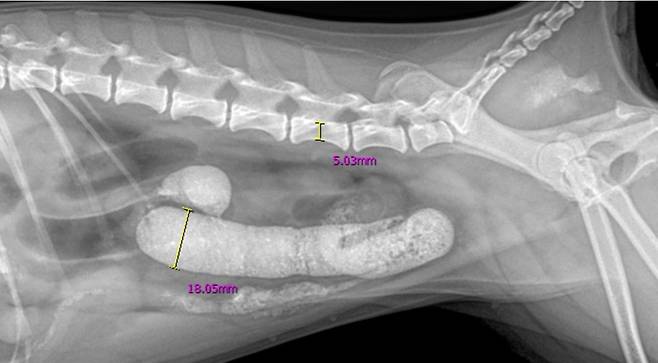

엑스레이 검사 결과, 소장이 기준치보다 심하게 확장된 장폐색 소견이 확인됐다. 치료를 맡은 홍영수 온동물의료센터 외과 원장은 단순 내과적 치료로는 해결이 어렵다고 판단하고 보호자와 상의 끝에 수술을 결정했다.

수술에서 소장 중간부터 말단까지 다량의 모래가 뭉쳐 있는 것이 발견됐다. 특히 해부학적으로 장 직경이 좁아지는 회맹부(회장과 맹장이 만나는 부위)에서 모래가 완전히 걸려 이동이 불가능한 상태였다. 이물질 제거를 위해 장을 절개해야 했다. 수술 후에는 복강을 여러 차례 세척해 2차 감염을 예방했다.